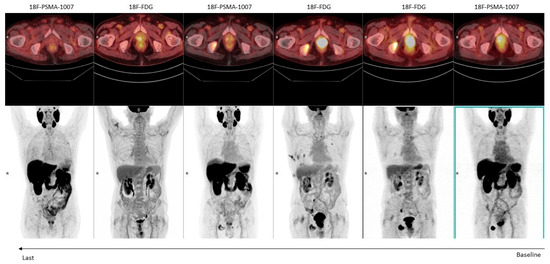

| Michalski et al. [48] | Germany 2021 | Retrospective bicenter | 54 | Assessment of mismatched lesions in mCRPC patients before RLT. | [68Ga]-PSMA-11 [18F]FDG | 33% of mCRPC patients show mismatched PSMA- [18F]FDG+ lesions and these patients present shorter OS. |

| Seifert et al. [30] | Germany, USA 2022 | Retrospective | 89 | Assessment of mismatched lesions in mCRPC patients before RLT. | [68Ga]-PSMA-11 [18F]-PSMA-1007 [18F]FDG | 18% of patients had mismatched lesions between PSMA and [18F]FDG PET, however only 3% of patients had mismatch findings not detected using only PSMA PET. |

| Chen et al. [42] | China 2022 | Retrospective | 56 | To assess metabolic heterogeneity of mCRPC patients | [68Ga]-PSMA-11 [18F]FDG | [68Ga]-PSMA-11 PET/CT showed higher detection rate than [18F]FDG PET/CT (75% vs. 51.8%). However, 23.2% of patients showed at least 1 mismatched PSMA- [18F]FDG+ lesion. |

| Güzel et al. [49] | Turkey 2023 | Retrospective | 71 | To investigate the prognostic role of dual-tracer PET imaging in [18F]FDG+ mCRPC treated with chemotherapy | 68Ga-PSMA-11 [18F]FDG | Volumetric parameters and Pro-PET scores obtained from dual-tracer PET/CT imaging predict OS in patients with mCRPC treated with taxane chemotherapy. Dual-tracer imaging should be performed in these patients as 78.9% of visceral metastases were PSMA−/FDG+ |